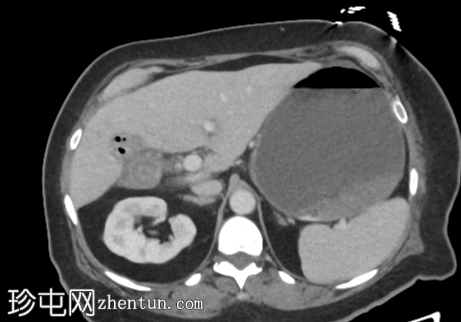

CT

轴位增强扫描(门静脉期)

胆结石引起的高度小肠梗阻(胆结石性肠麻痹)

胆结石已侵蚀穿过胆囊壁进入十二指肠,形成胆囊十二指肠瘘

胆囊壁增厚,胆囊周围脂肪浸润,符合并发胆囊炎的影像学表现。胆囊窝内可见游离气体,但其他部位未见游离气体

胆囊颈或胆囊管内嵌顿胆结石